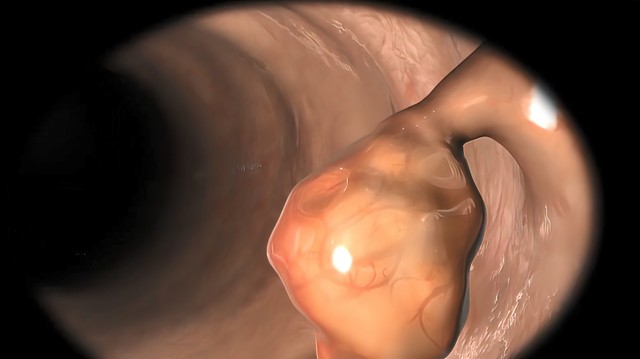

Polipból vastagbélrák: így alakul ki a rosszindulatú daganat?

Milyen tünetekről ismerhetjük fel a vastagbélpolipot, és hogyan alakulhat ki belőle vastagbéltumor?